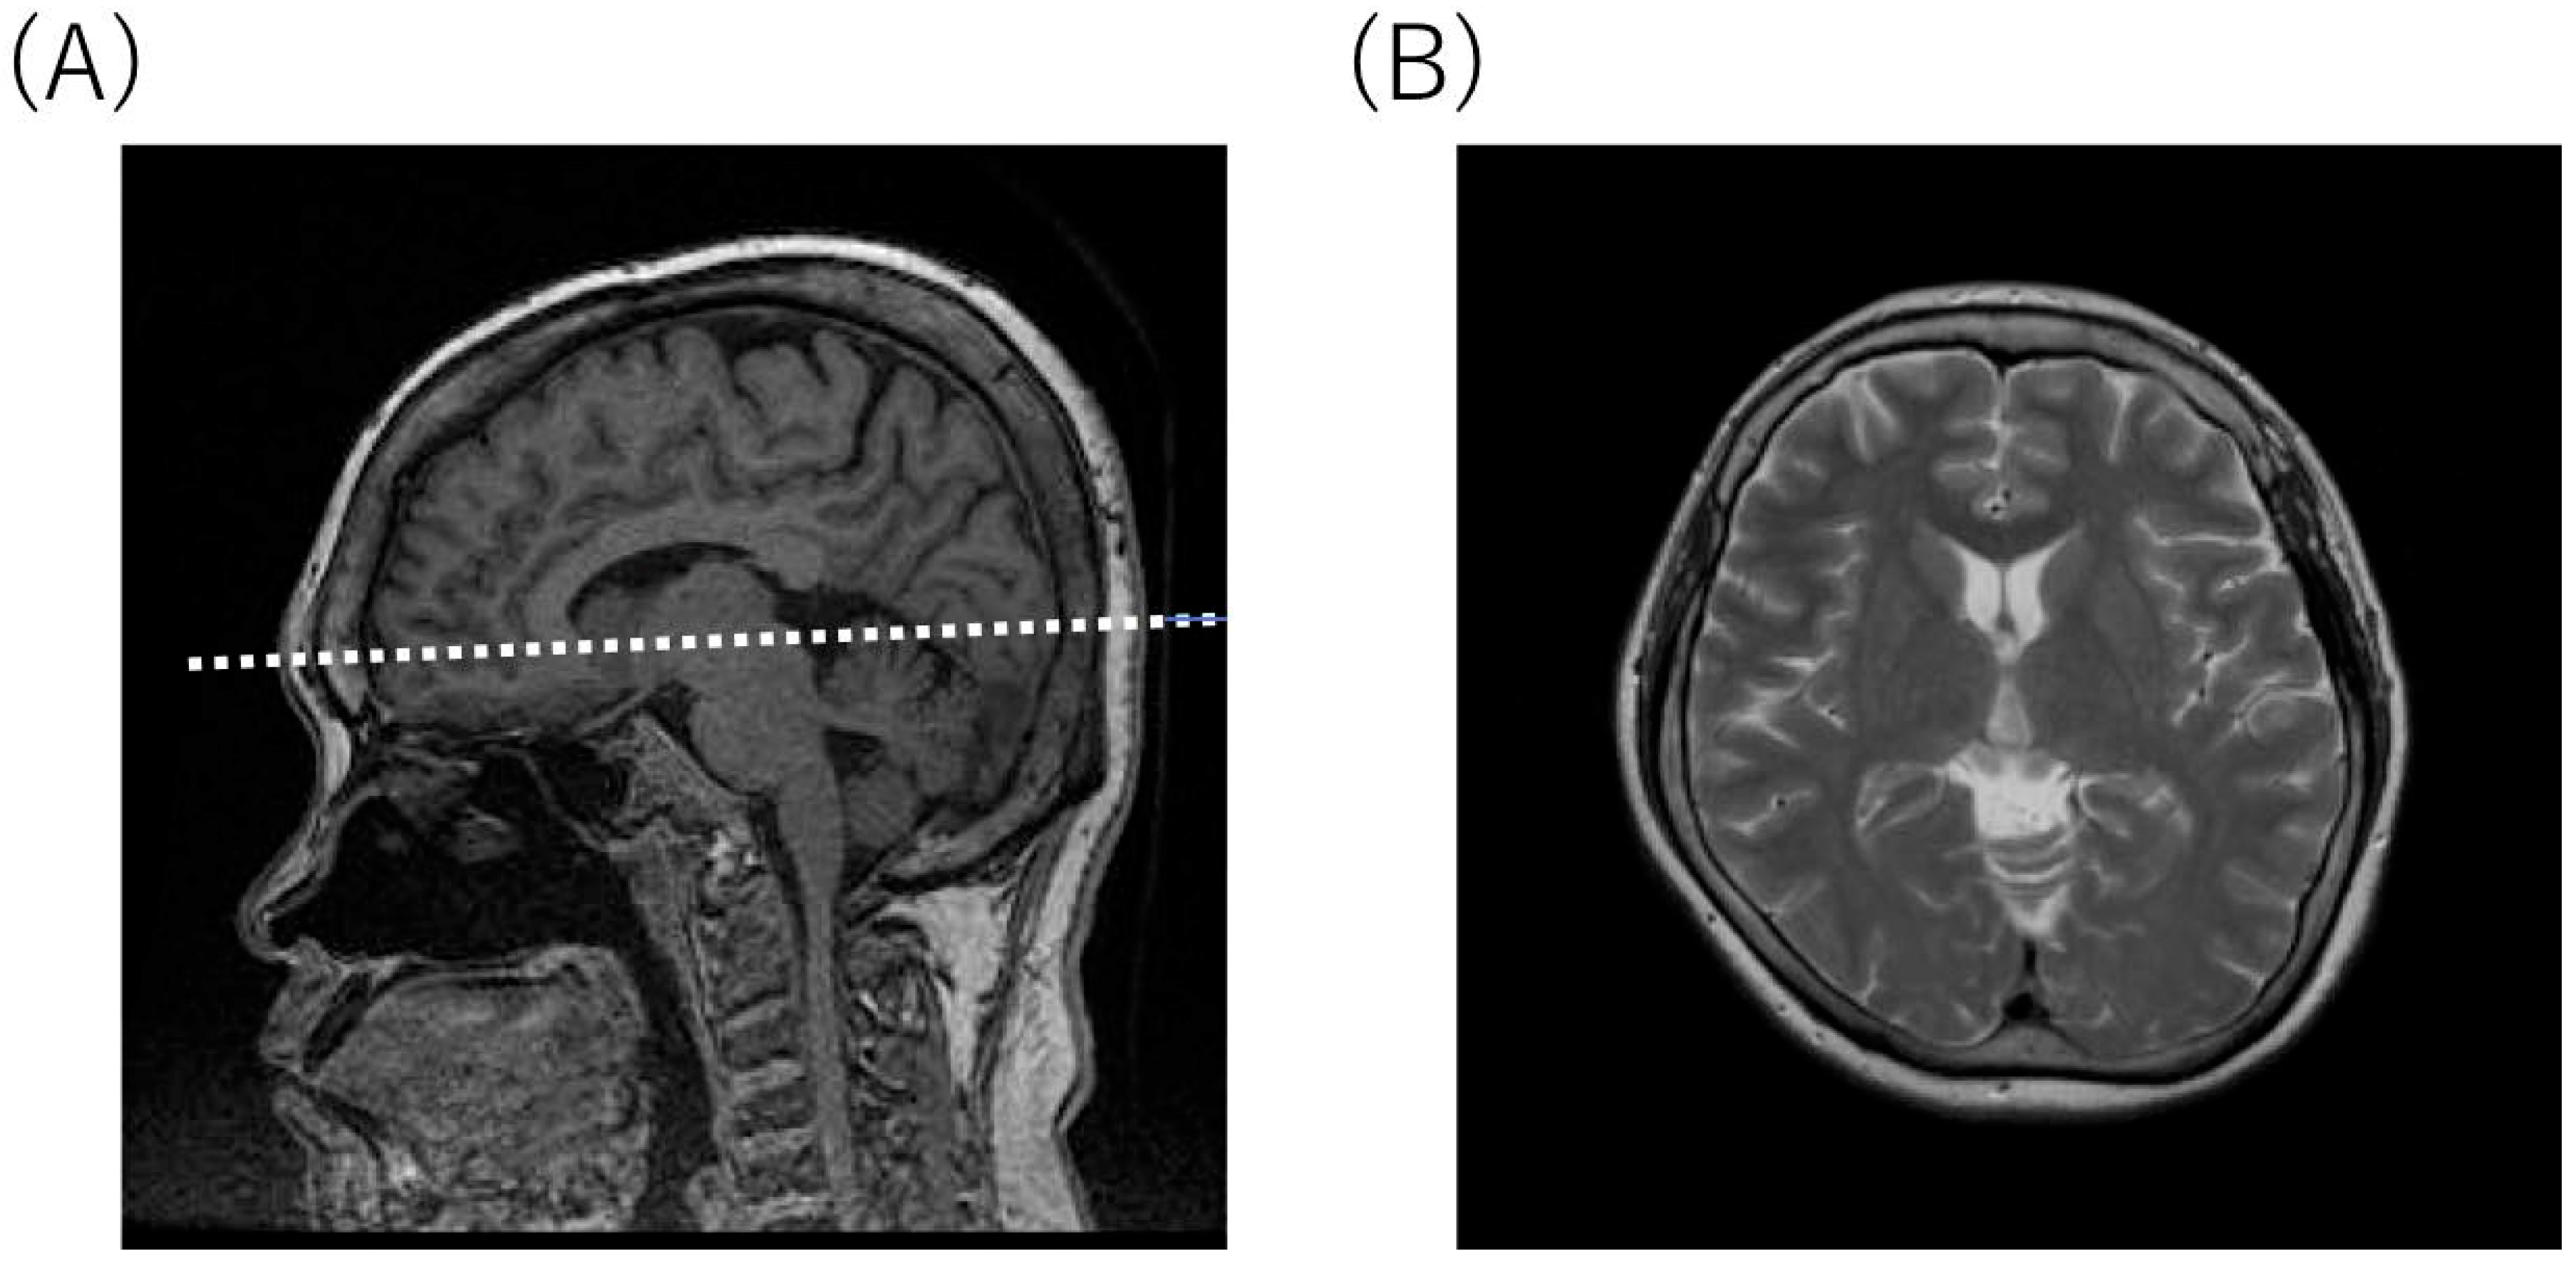

2.4. Radiological Findings